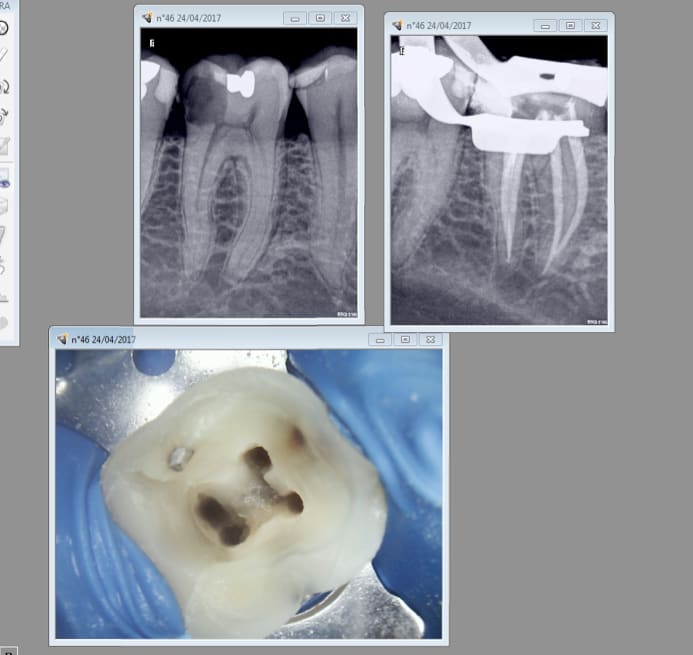

4 endos molaires aujourd'hui. Réglé comme du papier à musique ce petit localisateur d'apex chinetoque. -)

Et encore une couronne sur dent vivante qui foire une ! -)

Ca a bien le temps de se calcifier avant de crever ca ne rend le chalenge de trouver le mv2 que plus intéressant. -)